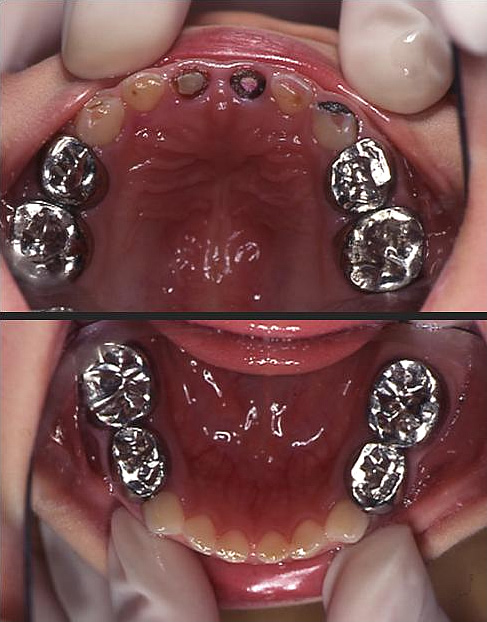

しかし口腔内には、C2・C3が14本も見られる。

(図1)

(図4 処置終了後の口腔内写真)

処置終了後の口腔内写真